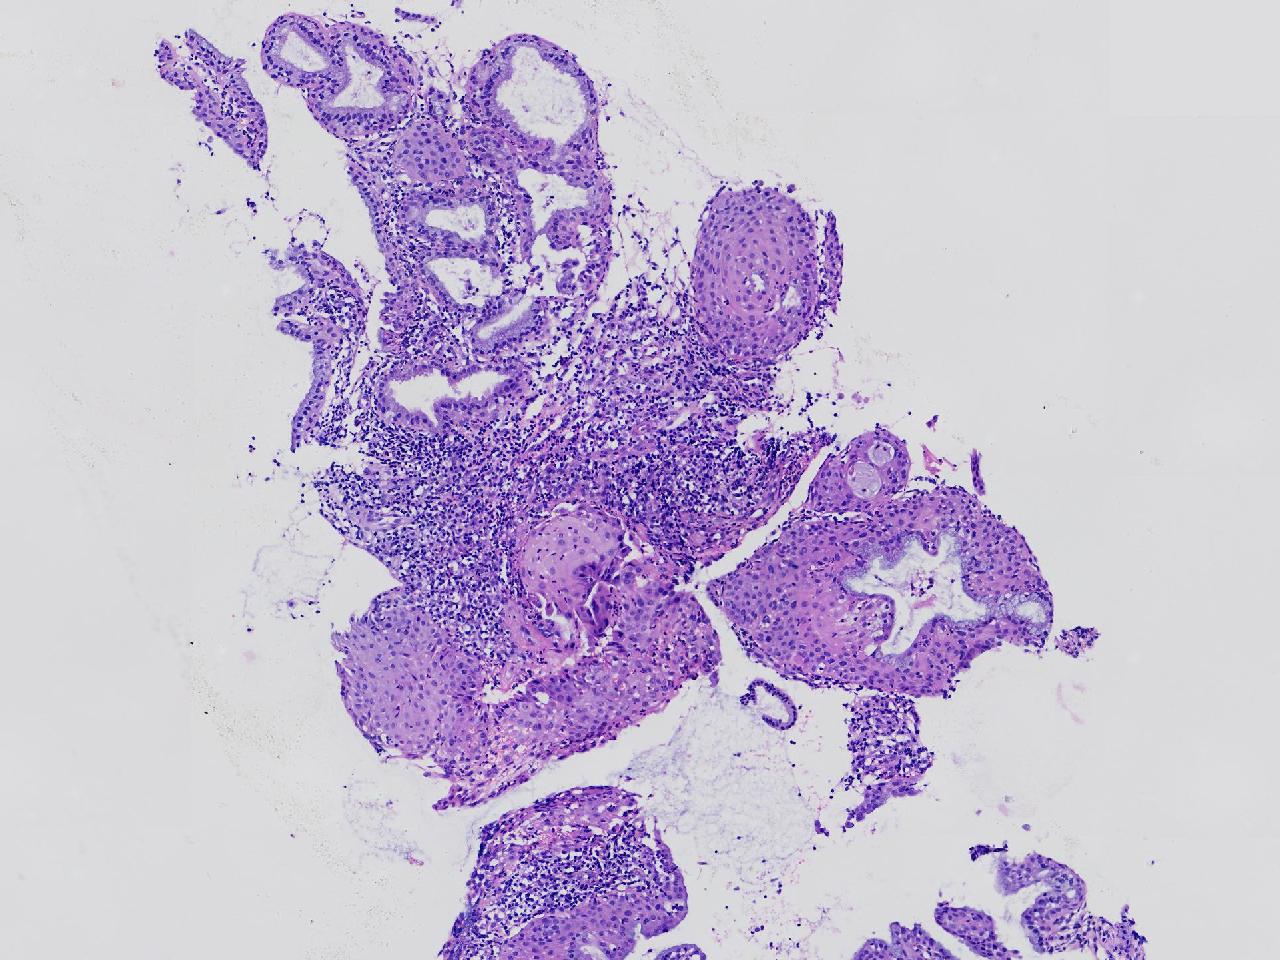

宫颈活检,有没有CIN?

女

36岁

宫颈病变

TCT示:ASC-US,HPV不详。

宫颈活检

图4

慢性宫颈炎伴腺上皮鳞化。

(宫颈活检组织) 慢性炎,储备细胞增生伴鳞化。